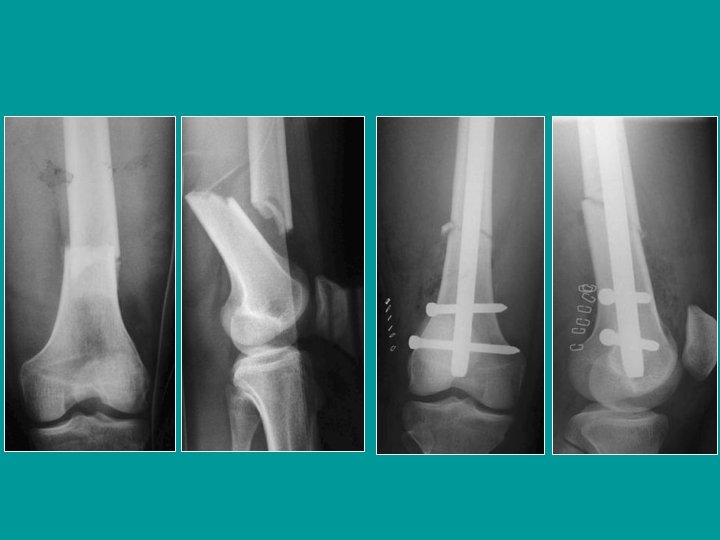

Fracturas Unicondíleas verticales de Trélat Atornillado transversal simple o placa

Fracturas Unicondíleas Horizontales de HOFFA Atornillado transversal en descenso (en rappel). Las cabezas de los tornillos están hundidas bajo el nivel del cartílago

Clavo endomedular retrógrado Introducción desde la rodilla (por debajo de la tróclea) estabilización con tornillos en las 2 extremidades

Clavo retrógrado: movilización precoz